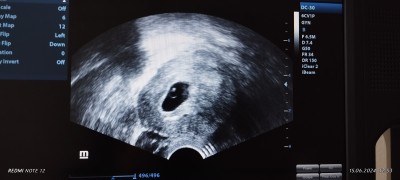

Kizlar cumartesi dr kontrolum vardi dr kese buyuk ikiz olma ihtimali var sizce var mi?8kaybim var olursa Allahin izniyle mucizem olucak

Bu arada gortuntu vajinal

Gebelik haftası 6+3

Ben bitane yolksalk gibi yani besleyici kese ve bebek olarak iki nokta görüyorum bitane bebek var gibi ama bi hafta sonra falan daha belli olur hayırlı olsun inşallah sağ Salim kucağınıza almayı nasip etsin Allah

Bu haftada taşlı yüzük gibi olur ultrason fotoğrafları yani iki ayrı nokta gözükebilir

İkiz için ayrı iki kese vveya tek kesede ayrı iki besleme noktası olması lazım ama daha net bişi denmemesi normal tam belli değiş şuan

Ben kadın doğumda çalışmıştım 5 yıl sanırım senin tek yumurta ikizi bir kese iki embriyo var gibi gözüküyor sağlıklı bir gebelik geçirirsin inşallah

Ben acibademde çalıştım 5 yıl  ister istemez birşeyler öğreniyorsun. Ama ben kesin gibi konuşmadım yanlış anlaşılmasın lütfen. Evet besleyici kese var ama yukerida ki embriyoda iki nokta var gibi 1 hafta daha dayan birde bence tabi bir doktora daha gozuk tek doktorun sözüyle kalma inşallah ikizdir o zaman çok istiyorsun madem

Öncelikle hayırlı olsun sağlık la kucağına alirsin inşallah venim amcamin ikiz kizlari var inanki  ayni hic fark yok resmi ama aticamda sana yuklyemyorum  onunda iki nokta tek yumrta ikizi ikizlerde olyus biri buyuk biri kucuk olyo ondan nokta gipi ne istersen o olsun hakinda hayırlısı

bende böyledi 6 haftalıkken öğrendim ikiz yol keseside ayrıydı o zamnla kay boldu siznki yakında göz gibi nie acbA

Tek yumurta ikizi demek bir kese var icinde iki bebek var bazen ikisininde ayri beslenme yeri olur bazen tek beslenme yeri olur.cift yumurta demekte 2 kese var yukarıdaki resimdeki gibi 2 yumurta 2 spermi dollemis  demektir beslenmesi gelisme keseleri ayri demektir.zqman gectikce ogrenirsin bende hicbirini bilmiyordm :) cift yumurta ikizlerm suan 12 haftalık dogumu bekliyoruz ayrica 2 yasinda bi kizimda var hamdolsn.zamanla hepsini ogrenirsin simdi ck heyecanlisin kayiplarn cokmus hakkimda hayirli olani nasip et de Allaha tevekkul et meryemcm